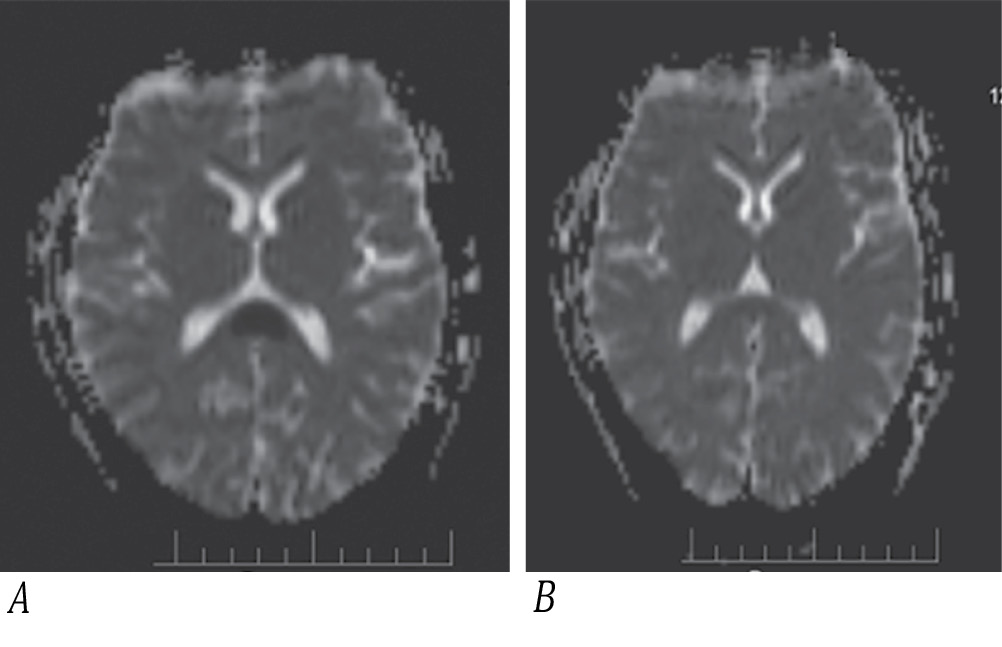

Рис. 3. МРТ пациента А. на ADC карте.

А — 1-й день госпитализации, низкая интенсивность сигнала в проекции ВМТ; В — 13-й день госпитализации, средняя интенсивность сигнала в проекции ВМТ.

Fig. 3. ADC Map MRI of Patient A.

A: day 1 of hospitalization, low signal intensity in the splenium projection; B: day 13 of hospitalization; average signal intensity in the splenium projection.